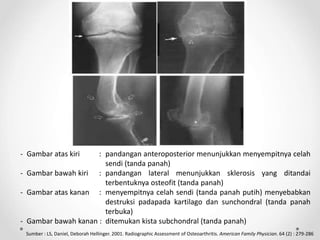

- Gambar atas kiri : pandangan anteroposterior menunjukkan menyempitnya celah

sendi (tanda panah)

- Gambar bawah kiri : pandangan lateral menunjukkan sklerosis yang ditandai

terbentuknya osteofit (tanda panah)

- Gambar atas kanan : menyempitnya celah sendi (tanda panah putih) menyebabkan

destruksi padapada kartilago dan sunchondral (tanda panah

terbuka)

- Gambar bawah kanan : ditemukan kista subchondral (tanda panah)

Sumber : LS, Daniel, Deborah Hellinger. 2001. Radiographic Assessment of Osteoarthritis. American Family Physician. 64 (2) : 279-286